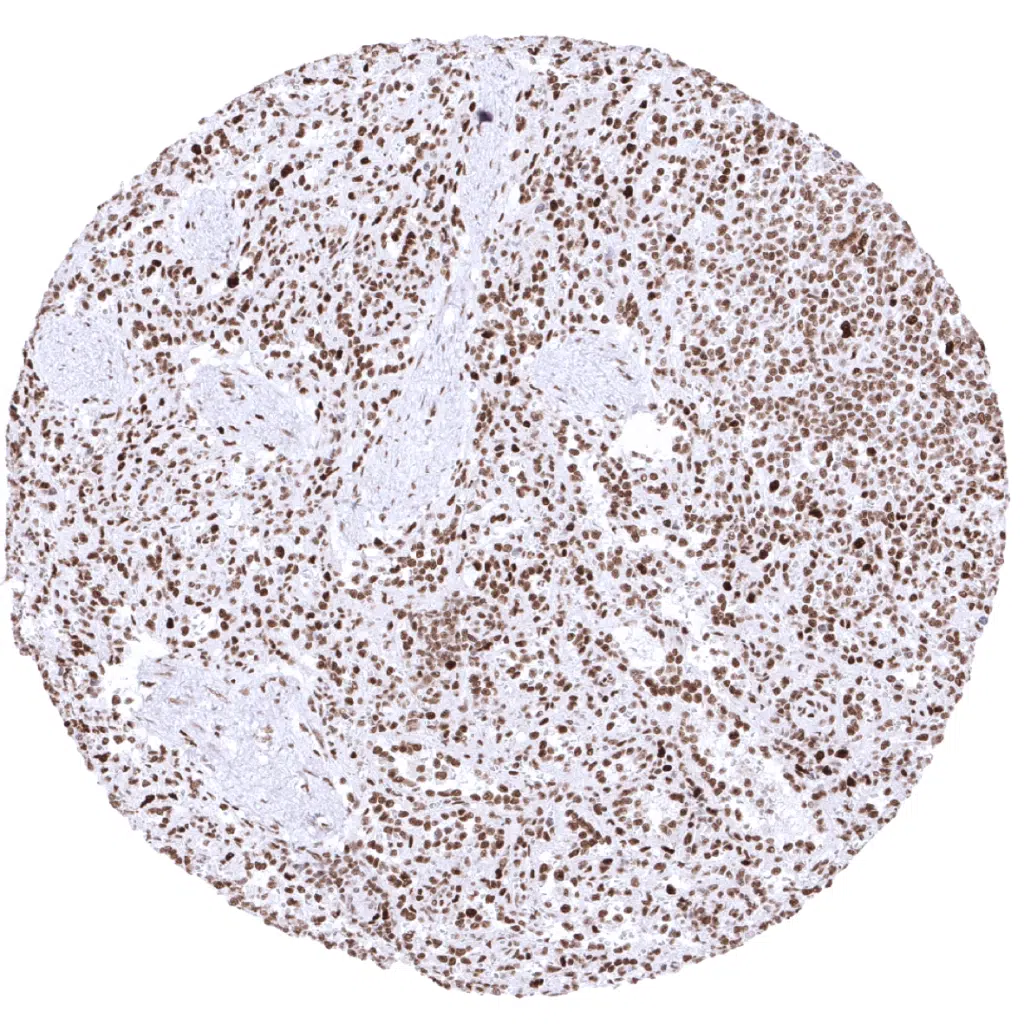

Lymph node